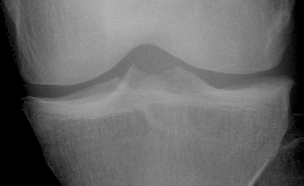

With these requirements in mind we experimentally come up with a layout comprised of six rectangular ROIs, two placed in femoral condyles and four in the head of tibia (cf. Figure 1).

Refer to captionF0subscript𝐹0\displaystyle F_{0}F1subscript𝐹1\displaystyle F_{1}T0subscript𝑇0\displaystyle T_{0}T1subscript𝑇1\displaystyle T_{1}T2subscript𝑇2\displaystyle T_{2}T3subscript𝑇3\displaystyle T_{3}med.lat.

Figure 1: Anchoring ROIs.

For consistency across the population we anchor the ROIs at anatomically meaningful landmarks and scale them proporionally.